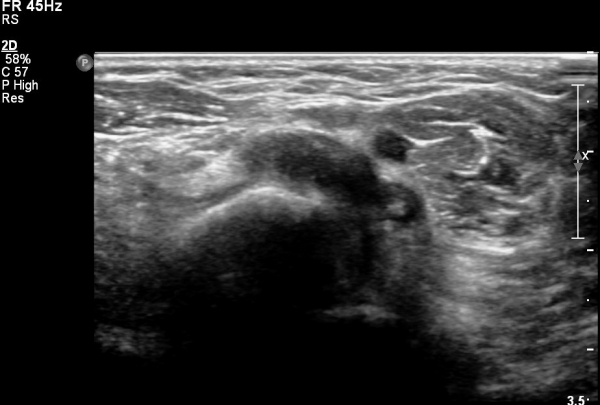

ŽÃËÀÚ¸¦ ¸»´ÜºÎ·Î À̵¿ÇÏ´Ï ¿ä°ñµ¶±â ÀÌµÎ¹Ú±Ù°Ç ÂøºÎ¿¡¼­ °ÏÀÌ Àú¿¡ÄÚ ºÎÁ¾ »óÅ·Π°üÂûµÇ°í(»çÁø 2)

Á¶±Ý´õ ¸»´ÜÀ¸·Î À̵¿ÇÏ´Ï °ÇÀÌ °üÂûµÇÁö ¾ÊÀ½(»çÁø 3).